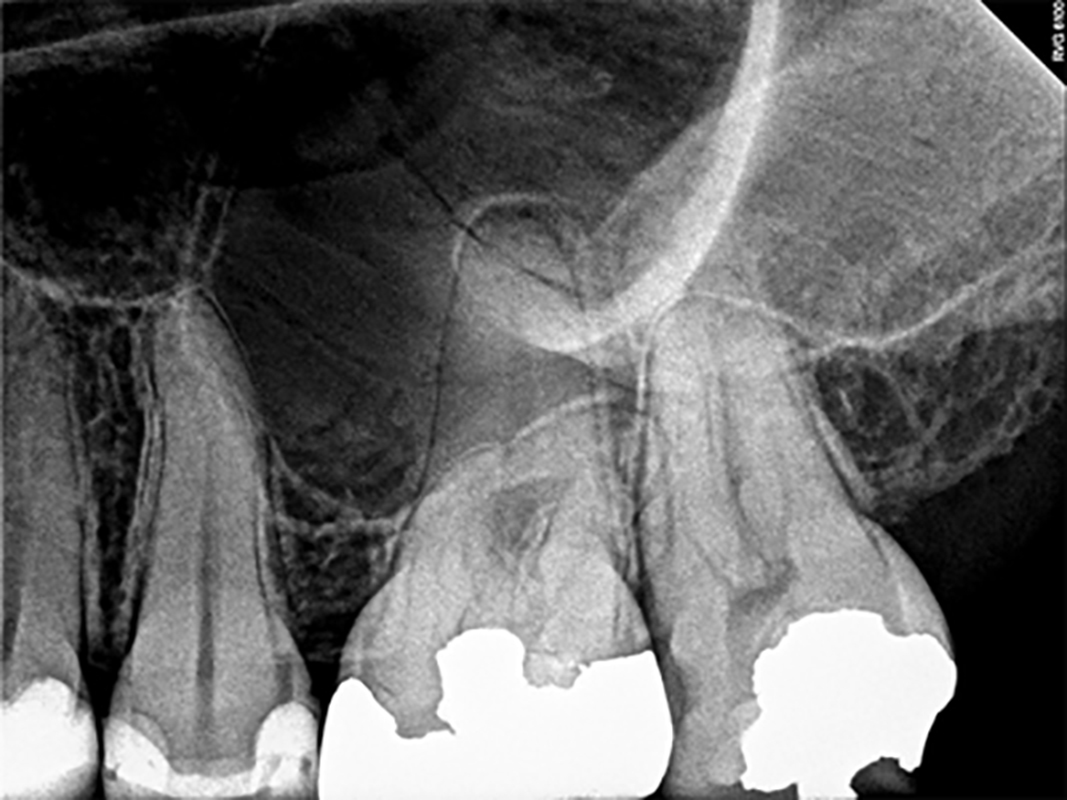

Optimal Canal Disinfection: Concepts, Materials And Evidence-Based Protocols

Canal disinfection, controlled memory nickel titanium, CBCT imaging, surgical microscopes, among other advances, have changed the clinical practice of endodontics dramatically in the past 20 years. CBCT provides a three-dimensional pre-operative guide to canal anatomy, which is subsequently interpreted through the microscope clinically (Fig. 1). Controlled memory nickel titanium instruments provide a faster, more predictable, … Read more